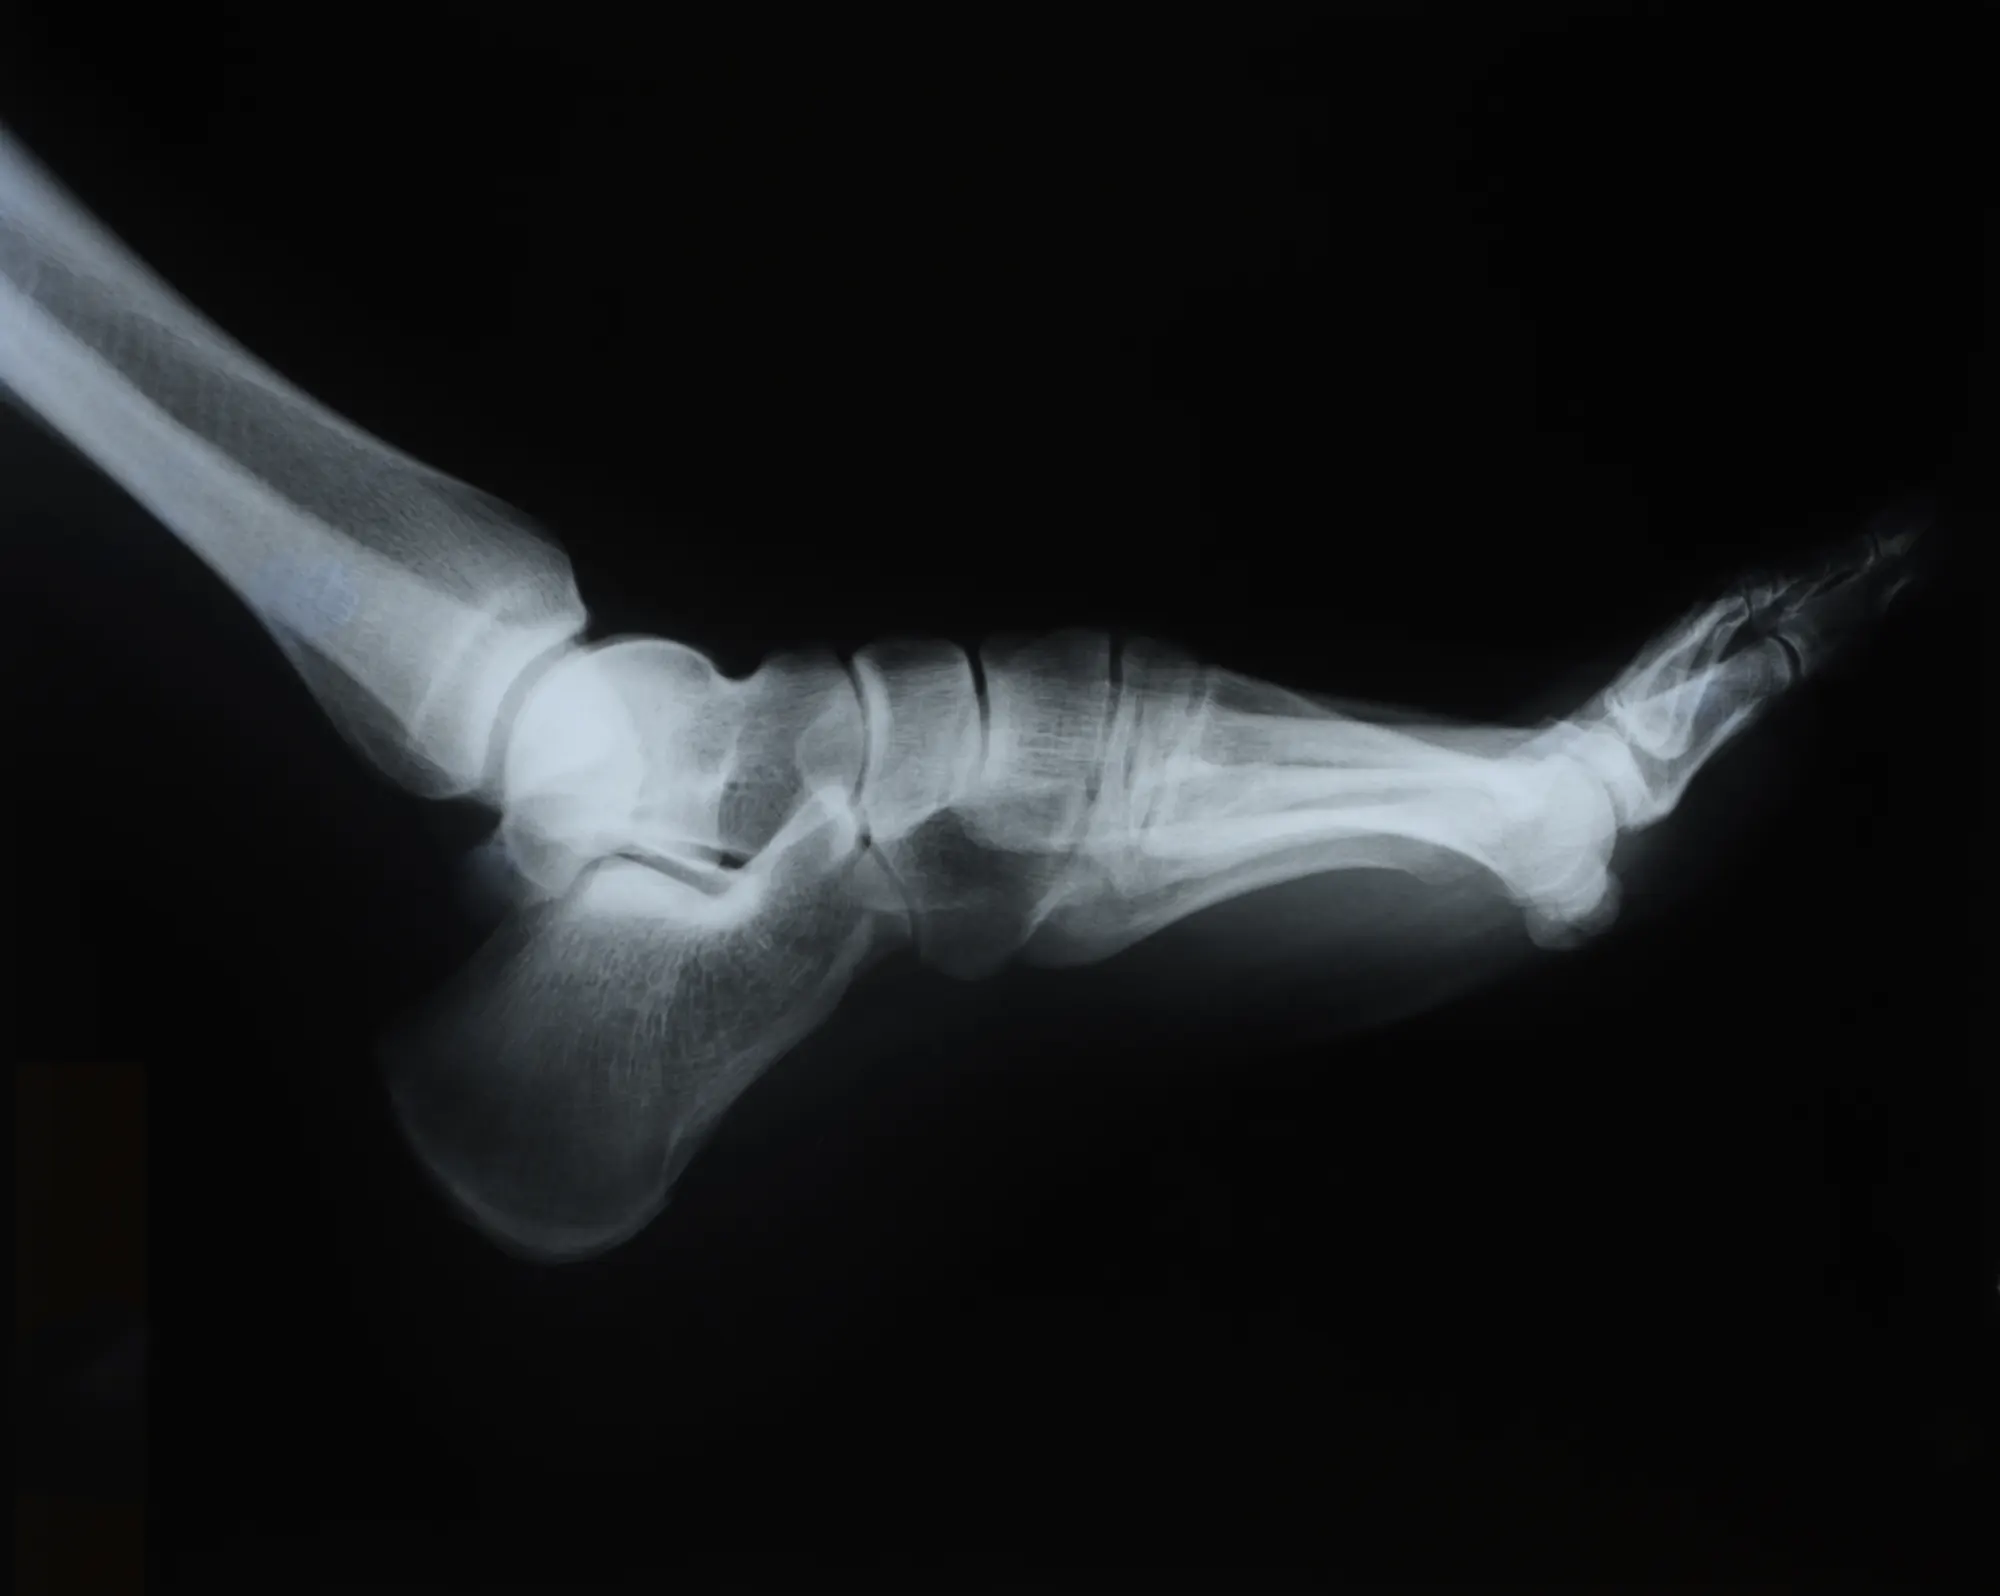

Por otro lado, gracias a la tecnología de Rayos X de última generación proporcionada por el Flat Panel podemos realizar exploraciones biomecánicas y diagnósticos certeros y con ello el resultados de los tratamientos mejora significativamente.